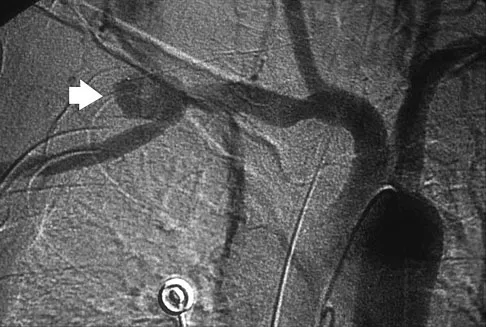

Question 39High Yield

What vessel is marked with an asterisk in Figure 44?

Explanation